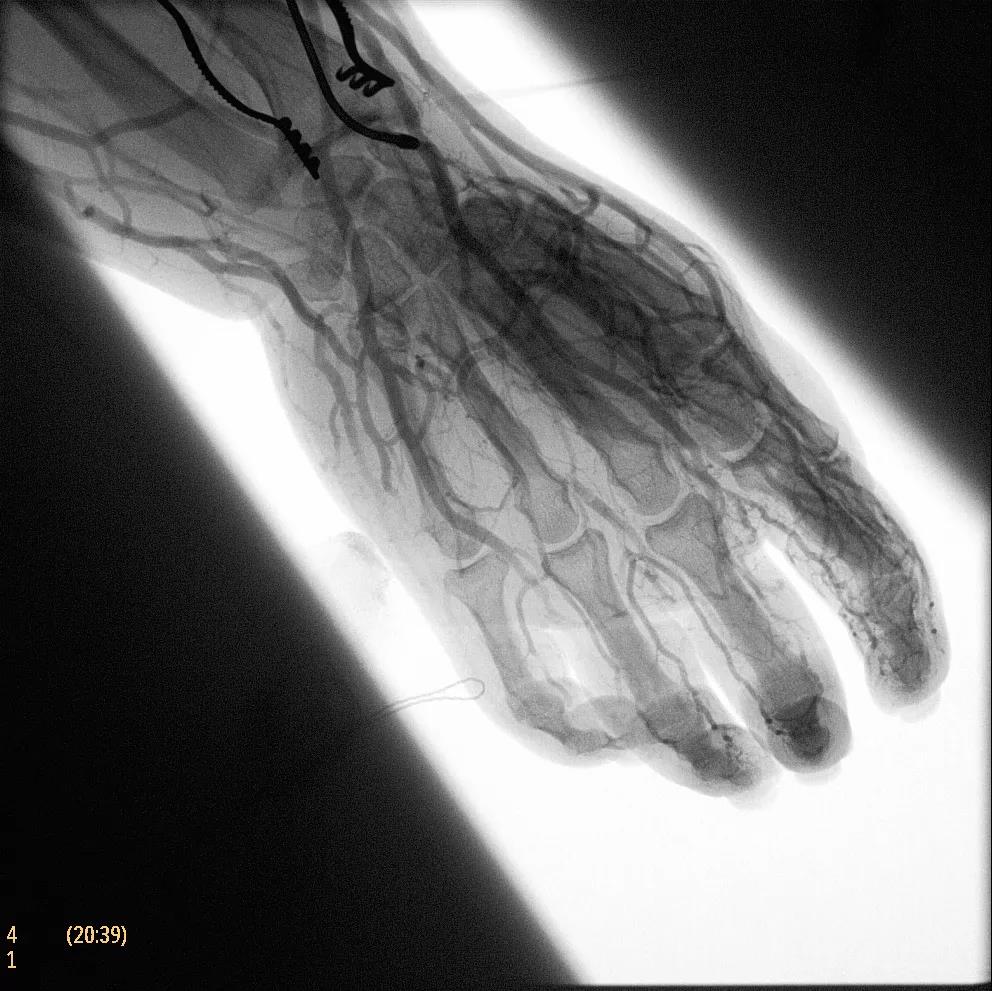

飛利浦于2019年2月18日宣布推出帶扁平探測(cè)器的移動(dòng)式C臂Zenition 70。Zenition 70使用飛利浦第四代Flat Detector系統(tǒng),具有卓越的成像清晰度和靈活性,可執(zhí)行各種情況。

據(jù)器械之家了解到,移動(dòng)式C型臂是X射線系統(tǒng),可帶入手術(shù)室(OR),在整形外科、創(chuàng)傷和血管手術(shù)等各種手術(shù)過(guò)程中提供實(shí)時(shí)圖像引導(dǎo)。Zenition70使醫(yī)院能夠最大限度地提高OR性能,增強(qiáng)臨床能力并為員工提供高質(zhì)量的用戶體驗(yàn)。

( Zenition 70匯集了圖像捕獲,圖像處理,易用性和多功能性方面的創(chuàng)新。)

在快速增長(zhǎng)的圖像引導(dǎo)微創(chuàng)手術(shù)領(lǐng)域 ,手術(shù)干預(yù)的范圍和復(fù)雜性在繼續(xù)增加,需要治療的患者數(shù)量也在增加。為了以更低的成本治療更多的患者,醫(yī)院需要具有不同能力的多功能C臂組,以便容易地適應(yīng)不同類型的手術(shù)和不同操作者的需要。Zenition 70易于在手術(shù)室之間移動(dòng),易于在患者周圍定位并且操作直觀。

飛利浦Zenition 70支持整個(gè)醫(yī)療保健機(jī)構(gòu)提高OR性能。平臺(tái)類似平板電腦的用戶界面和簡(jiǎn)單的統(tǒng)一工作流程意味著一旦操作員學(xué)會(huì)在平臺(tái)上使用一個(gè)系統(tǒng),他們就可以輕松地操作它們。該系統(tǒng)可在任何介入或外科手術(shù)過(guò)程中快速直觀地拍攝傻瓜相機(jī)。Zenition的緊湊設(shè)計(jì),位置記憶功能(僅適用于Zenition 70)和BodySmart軟件,即使在圖像增強(qiáng)器或平板探測(cè)器的邊緣也能捕捉快速一致的圖像,將C臂重新定位的需求減少45%。

( Zenition 70采用與Azurion平臺(tái)相同的圖像處理算法。

為了獲得清晰的高質(zhì)量圖像,Zenition 70 采用了與公司Azurion平臺(tái)相同的圖像處理算法,可提供患者解剖結(jié)構(gòu)的高清可視化和更大的可視區(qū)域。飛利浦的MetalSmart軟件等功能可確保圖像質(zhì)量,該軟件可自動(dòng)調(diào)整圖像的對(duì)比度和亮度,以便在視野中存在金屬物體(如植入物)時(shí)提高圖像質(zhì)量 - 這一特性使Zenition 70在整形外科中特別有用。